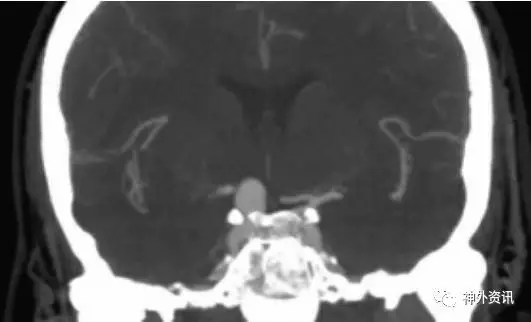

图1. 该动脉瘤的部分瘤颈被前床突遮蔽。硬膜内前床突切除术则可显露瘤颈以行夹闭。请参见下面的图片。

图5. 对于巨大床突旁动脉瘤,首先需打开侧裂,显露视神经和颈内动脉分叉部。如同该例右侧病例显示的,动脉瘤瘤颈的近端部分常常被前床突遮挡。十字切开前床突硬脑膜;必要时,切口可根据病变情况向更外侧或更内侧延长(插图)。